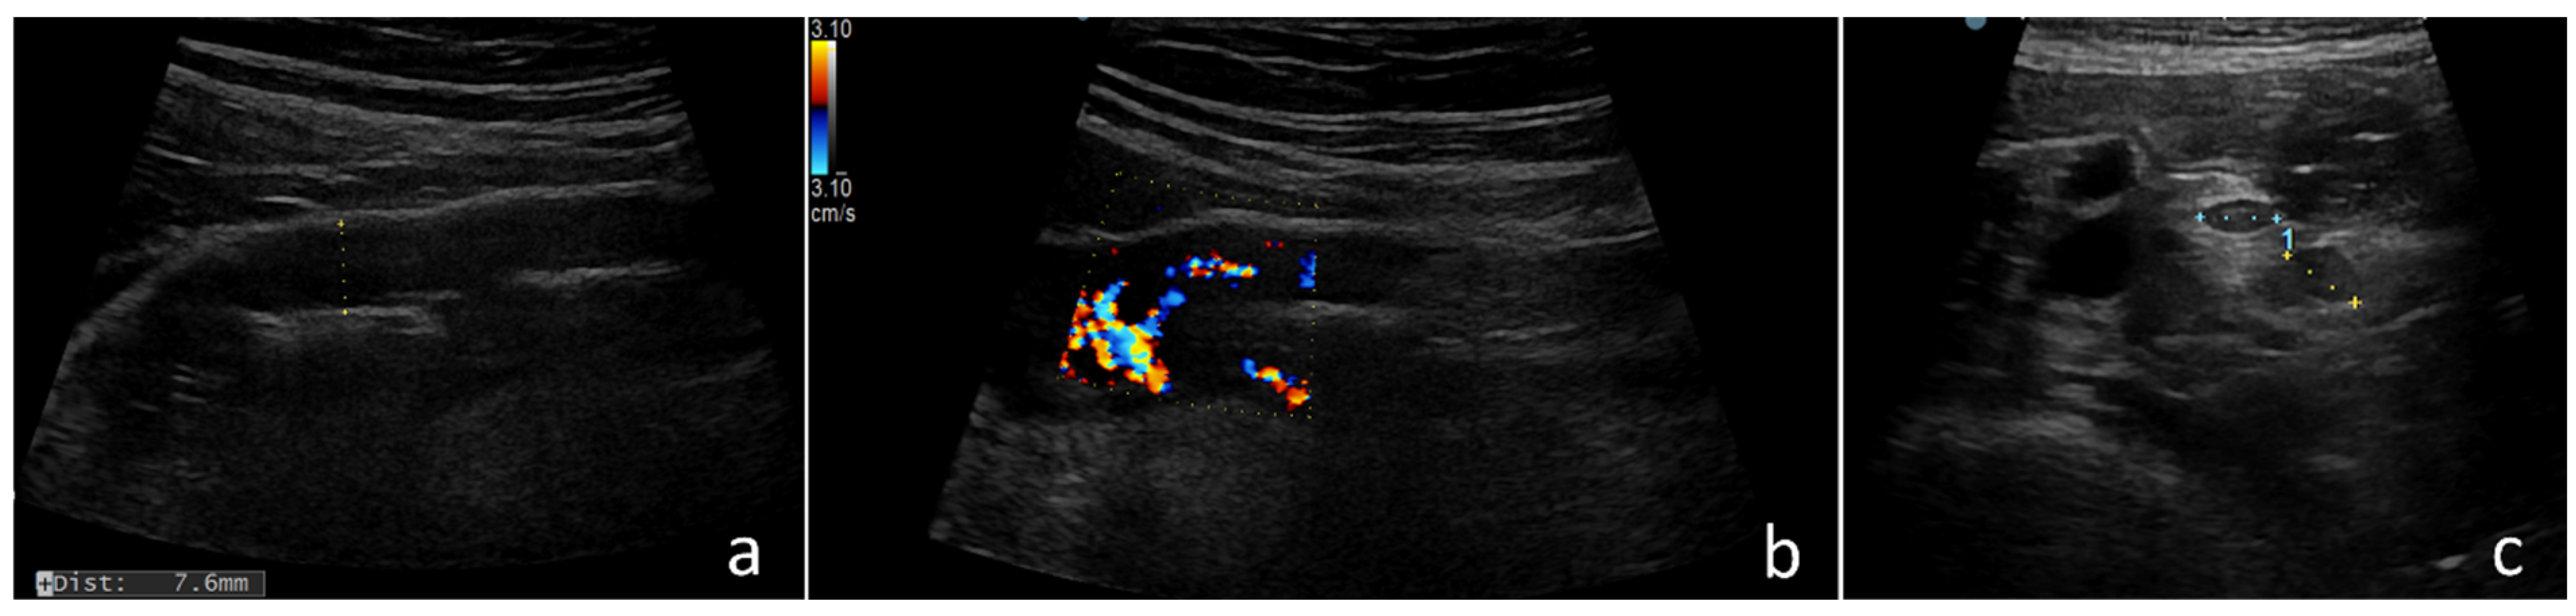

2.3. Ultrasound